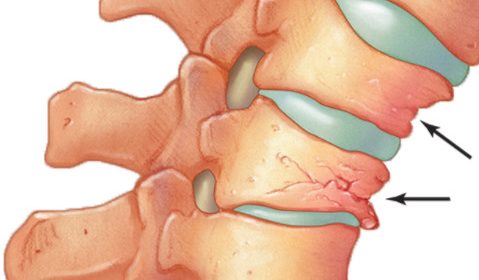

椎體成形術俗稱打骨水泥,是以針孔微創的手術,把人造骨粉(丙烯酸膠粘劑)注射到脊椎椎體骨折下陷的地方,強化並鞏固因骨質疏鬆導致脆弱的骨骼,重建椎體的骨骼形狀以防止下陷前傾的骨椎進一步惡化(見圖二至五)。適合進行椎體成形術的情況包括(1)因骨折造成的持續腰背痛;(2)因嚴重骨質疏鬆致骨骼脆弱,脊骨前傾及出現駝背現象;(3)任何藥物都起不了作用。這項小手術只須一小時的時間,病人可在術後24小時回家,不須再服止痛藥,但須服用抗骨質疏鬆藥物,來預防脊椎、盤骨或其他部位骨折及下陷。

圖二

圖三

椎體成形術是以針孔微創的手術,注射人造骨粉(丙烯酸膠粘劑)到脊椎椎體